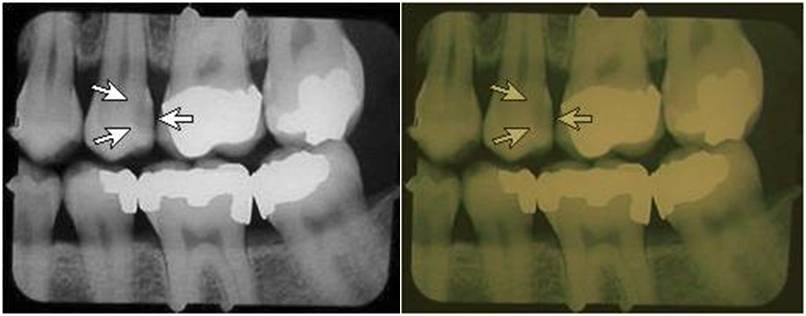

Digital dental radiography uses x-rays the same as film imaging and also results in x-ray doses to your patients and staff. Digital offers the potential for significant reductions in x-ray dose. However, it has been our experience that about 25% of the offices that switch to digital dental are using doses similar to or higher than D-speed film! D-speed film usually requires a dose of about 200 mrad. Digital doses should be on the order of 50 to 75 mrad, a reduction in dose of 60 to 75%.

You should have your present doses measured, a service provided by DIQUAD, LLC via mail through the DIQUAD website image upload system. Your present exposure time should be about 25% to 45% of the exposure time you were using with D-speed film. For example, if your exposure time was 300 msec (0.3 sec) for D-speed film you should be using about 75 to 120 msec (0.075 to 0.12 sec) for digital imaging. If you were using E-speed film and an exposure time of about 200 msec (0.2 sec), your digital exposure times should also be about 75 to 120 msec (0.075 to 0.12 sec).